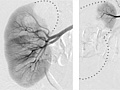

An angiogram is an X-ray test that uses dye and a camera to take pictures of the blood flow in an artery or a vein. An angiogram can be used to look at the arteries or veins in the head, arms, legs, chest, back, or belly. This test is done to look for problems in the arteries or veins.

During an angiogram, the doctor will put a thin, flexible tube into a blood vessel in your groin or arm. This tube is called a catheter. The doctor guides the tube to the blood vessel that will be studied. Then a dye is injected through the tube to make the area easier to see. X-rays or pictures are taken of the area.

When the catheter is in place, the dye is injected through it. You may be asked to take a breath and hold it for several seconds. Several X-ray pictures will be taken one after another. These will be available right away for your doctor to look at. You need to lie very still so the pictures are clear. More pictures may be taken.